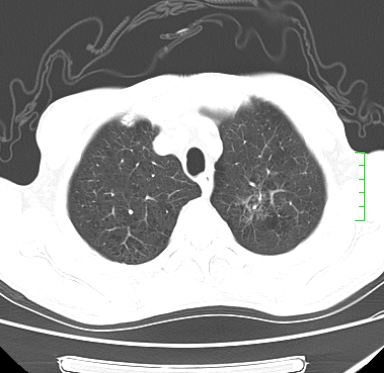

m,73y。膝关节疼痛伴双下肢水肿。入院常规胸片发现结节灶。增强为静脉期。

浅分叶、棘突,考虑右下肺周围型肺癌

肿块周围可见局限性气肿,考虑肺癌可能性大。双肺上叶继发型肺结核。

指套征,强化明显,近侧肺组织局限性肺气肿,考虑支气管类癌,慢支、肺气肿、双上陈旧性tb、冠脉钙化。

1)考虑右肺下叶周围型肺癌。2)右肺上叶及左肺感染性病变(结核可能)。3)肺气肿。4)冠状动脉钙化。